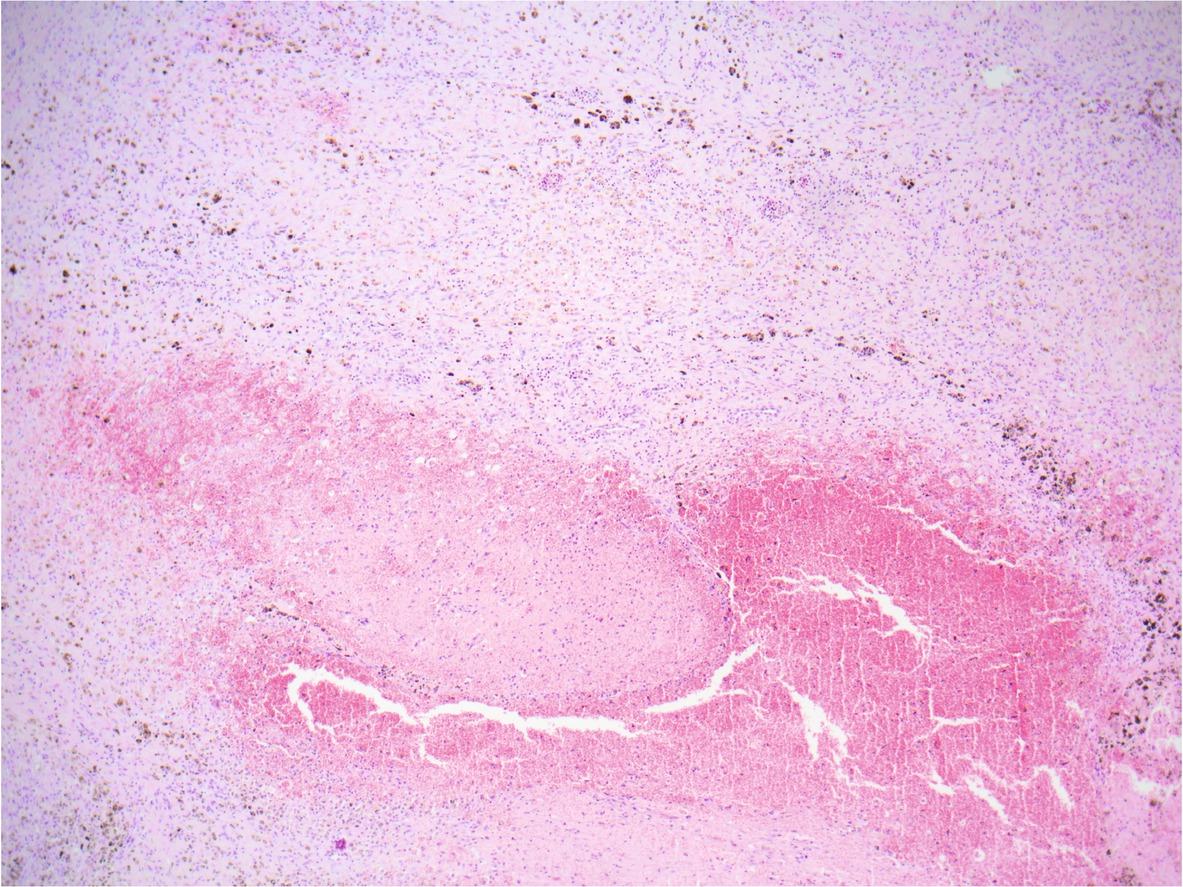

Lung, a segment of the migratory tract (channel) of F. magna. There is a mixture of fibrin, extravasated erythrocytes, and necrotic debris within the centre of the migratory tract (most of the lower half of the figure). Surrounding the centre (upper half of the figure) there is an elaborate immature fibrous tissue entrapping a few smaller and collapsed airways, and infiltrated by moderate numbers of lymphocytes, plasma cells, macrophages, and fewer neutrophils and eosinophils. Note numerous dark brown iron porphyrin pigment granules within the cytoplasm of the macrophages. Hematoxylin and eosin stain, 40X total magnification.

Lung, a segment of one smaller migratory tract (channel) of F. magna. Adjacent to lumen filled with erythrocytes there is a narrow layer of degenerated and necrotic inflammatory cells which is further bounded with an immature fibrous tissue of similar composition as described in figure 2. Note one medium-sized bronchiole and several collapsed and distorted airways which are filled with cellular and karyorrhectic debris and extravasated erythrocytes (left half of the figure). Hematoxylin and eosin stain, 100X total magnification.